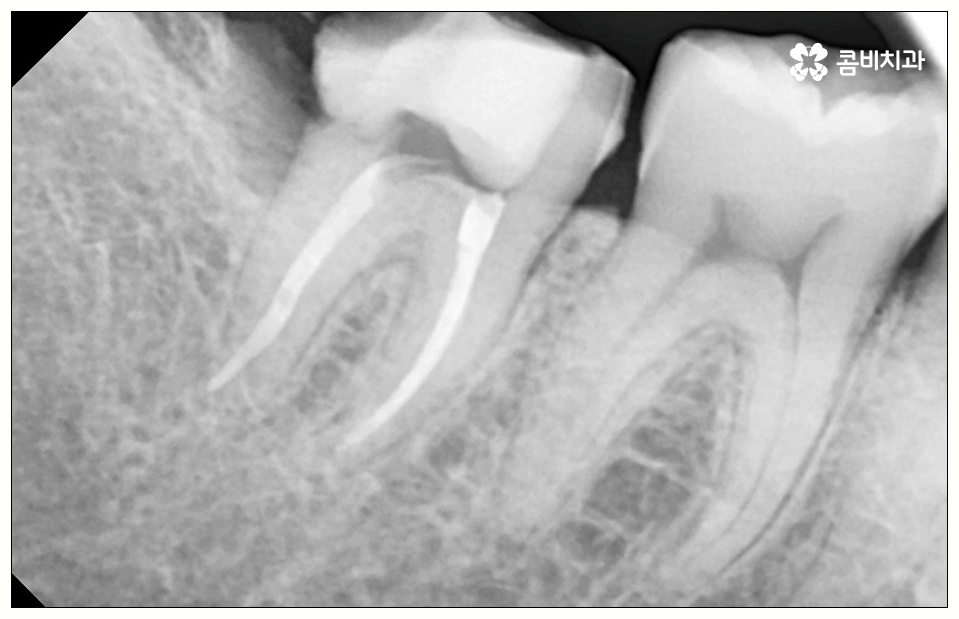

사랑니로 인해 어금니 사이 충치 가 발생하고 치아 파절이 일어나 신경까지 손상이 일어난 경우 원인이 된 사랑니를 발치한 후에 신경 치료와 크라운 처치를 통해 어금니 수복을 해 주게 되는데 이 때 근관 소독 및 밀봉 후 통증이 없어졌다고 해서 크라운 처치를 해 주지 않은 채로 치료를 마치게 되면 2차 감염이 일어나거나 외부 충격으로 인해 또 다시 파절이 생길 가능성이 높아 어렵게 살린 어금니를 잃게 될 수도 있으니 꼭 남아 있는 치아를 전체적으로 덮어주는 크라운 처치를 통해서 보호해 주시는 것을 권유드리고 있습니다.